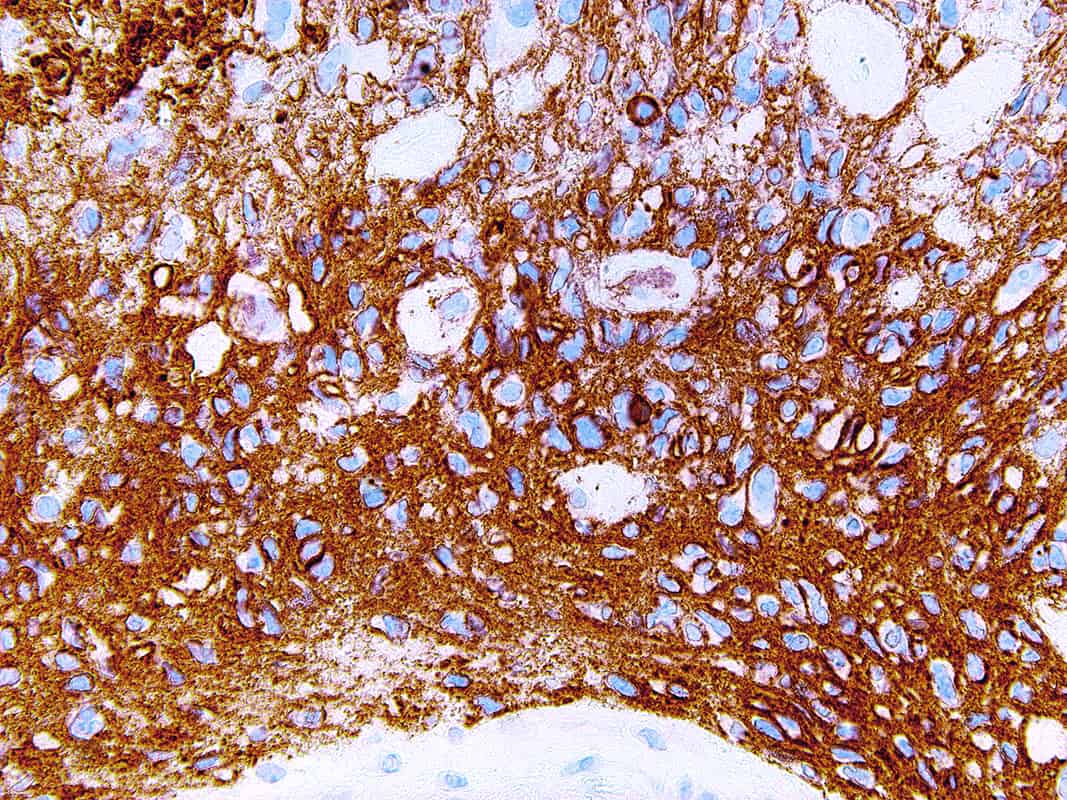

CD56

Cluster of differentiation 56 (CD56), also known as Neural-Cell Adhesion Molecule (NCAM), is a glycoprotein involved in synaptic plasticity, cell-cell adhesion, neurite outgrowth, learning, and memory. NCAM is expressed in normal neurons, glia, natural killer cells, activated T-cells, brain and cerebellum, neuroendocrine tissues, and skeletal muscle. Anti-CD56 recognizes a number of tumors including myeloma, myeloid leukemia, natural killer/T-cell lymphomas, neuroendocrine tumors, pancreatic acinar-cell carcinoma, pheochromocytoma, and Wilm’s tumor. CD56 is detectable in neoplasms that are neuroectodermally-derived, such as retinoblastoma, medulloblastomas, astrocytomas, small cell carcinomas, and neuroblastomas. It has also been linked to rhabdomyosarcoma, a tumor that is mesodermally-derived.

| Positive Control | Neuroblastoma |